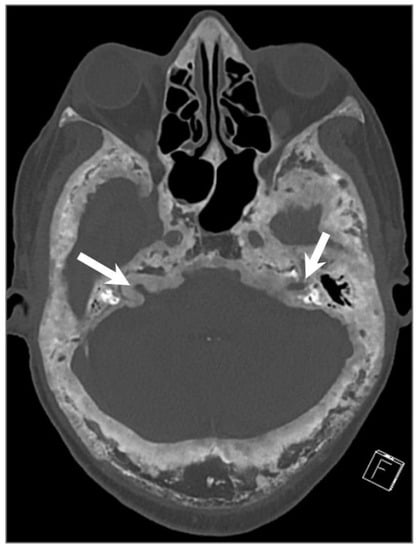

4.4.5. Paraganglioma